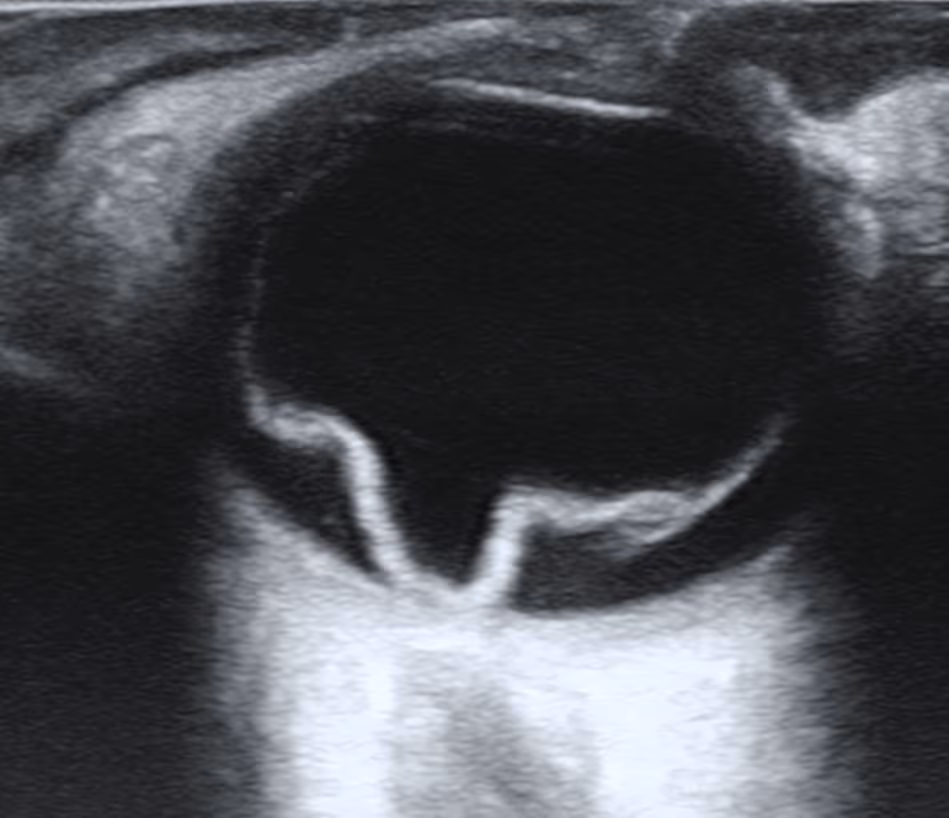

O nevus de coroide é uma lesão pigmentada benigna da camada vascular do olho — uma espécie de 'pinta' no fundo do olho. Quase sempre é inofensivo e descoberto por acaso em um exame de rotina, mas exige acompanhamento porque uma pequena parcela pode se transformar em melanoma de coroide. Entenda a diferença entre nevus, melanocitoma e melanoma, e como o oftalmologista acompanha essas lesões.